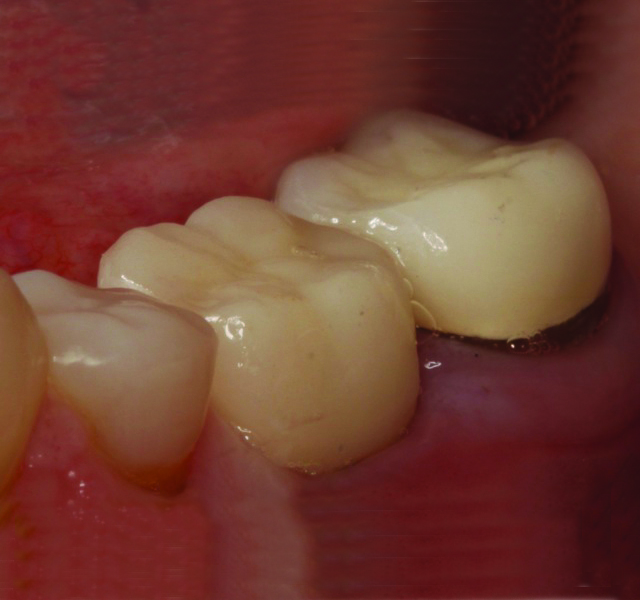

Thanks to the digitization of the final abutment, a monolithic e.max restoration was designed, milled, and ready for delivery prior to the office receiving the custom abutment. Upon delivery, the provisional restoration and solid abutment were removed. The new custom abutment was tried-in, along with the new e.max restoration to verify fit and occlusion. After the restoration was conditioned with Monobond Etch & Prime (Ivoclar Vivadent), the abutment was torqued to 35 Ncm, Teflon tape was placed in the screw access, and the restoration was cemented with SpeedCem (Ivoclar Vivadent) (Figure 5). Equigingival margin placement generated by the custom abutment design ensured thorough removal of excess cement. A post-operative radiograph was taken (Figure 6).

Fig 5. Teflon tape is placed in the screw access, and the restoration is cemented.

Figure 5

Fig 6. Post-operative radiograph.

Figure 6